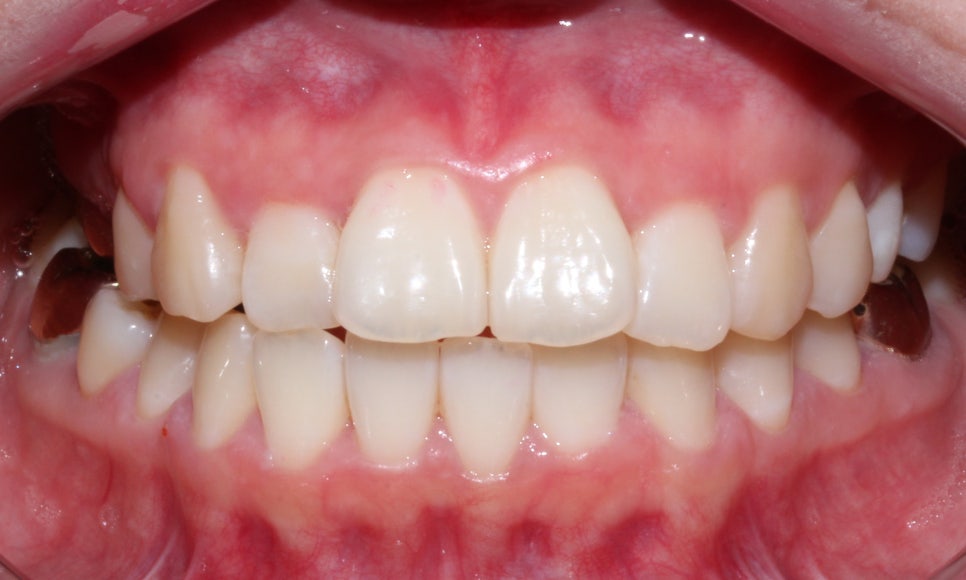

마무리 한 모습입니다.

브라켓을 붙이고 진행한 것은 아니라

디테일하게 중심선을 맞추거나

구치부 교합까지 완벽히 잡진 못하지만

환자분께서 원하시던

#12가 들어가 있던 모습과

뻗쳐보이는 느낌을 개선 후 마무리를 했습니다.

이렇게 투명교정을 통해

골격적 비대칭을 완벽히 해소하진 못해도

가지고 있는 골격 안에서

최대한 환자분의 니즈에 맞춰

교정을 할 수 있습니다.